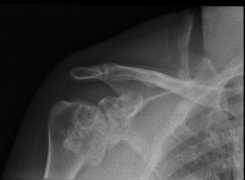

不久前,80岁高龄的陈奶奶在家不慎摔伤,导致左侧肩膀剧烈疼痛肿胀伴活动受限,遂来我院就诊。影像学检查发现,陈奶奶左侧肱骨近端呈严重粉碎性骨折并伴有严重骨质疏松。入院后,科室医疗团队充分考虑患者自身情况、功能要求等,经反复讨论,与患者及其家属充分沟通后,主任医师王小勇,副主任医师庄培峰、黄长智,主治医师李孛医疗团队制定了详细手术方案和应急预案,并成功为患者施行左侧人工反向全肩关节置换术,手术过程顺利,术后患者恢复良好,目前正在进行康复训练。

术前术后对比图